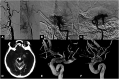

Case presentation: A 60-year-old woman with chronic hypertension rapidly developed right hemiplegia. She had been suffering from slight headache and abnormal sensation in the right limbs 1 week before the ictus. MRI demonstrated small acute infarctions in the left middle cerebral artery (MCA) territory. The left ICA was not visualized on MRA. Diffusion-perfusion mismatch was indicated by the automated image postprocessing system. Endovascular recanalization was planned to prevent the progression of cerebral infarction. After advancing a 5MAX ACE, initial left ICA angiography was performed, resulting in extravasation of contrast medium from the C2 segment of the left ICA. 3D rotational angiography revealed left ICA dissection of the C2 segment. To secure hemostasis, the patient underwent internal trapping at the C1 and C2 segments of the left ICA. Collateral flow to the left MCA via an anterior communicating artery was observed. On day 28, the patient was transferred to a rehabilitation hospital with right hemiplegia and motor aphasia.